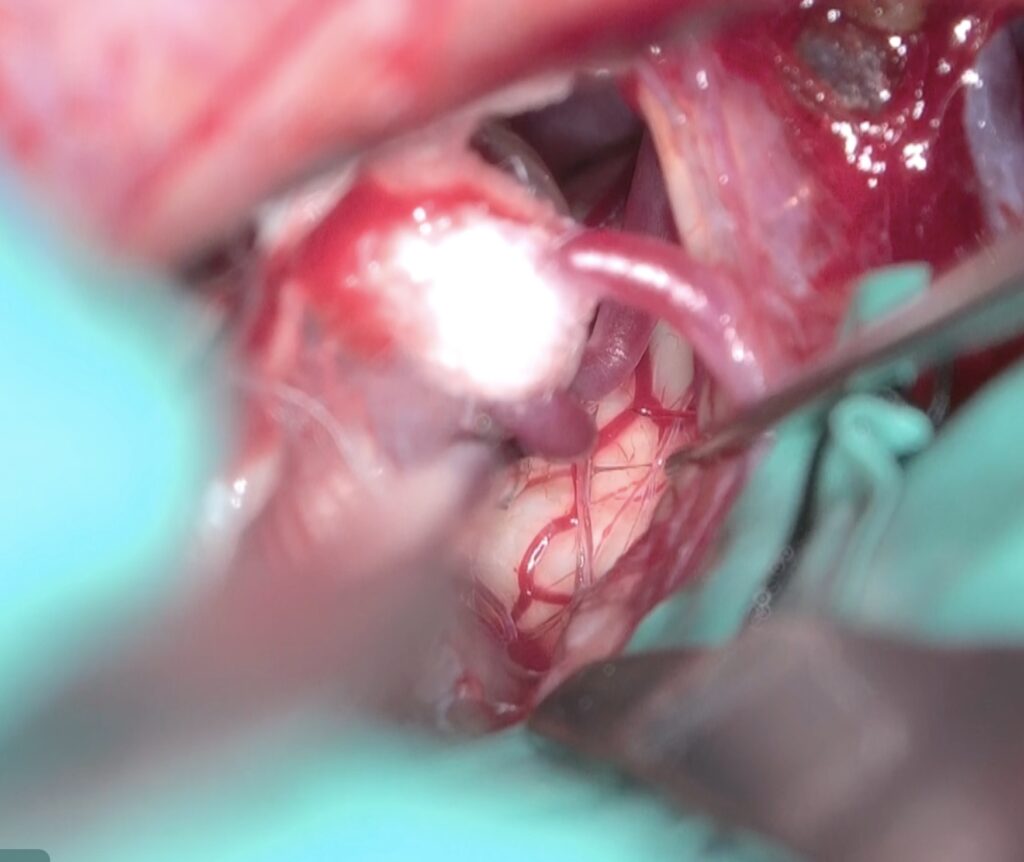

実際はPICAがREZを圧迫していました。